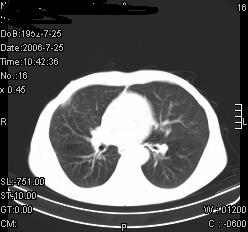

患者,男,54岁,咳嗦,咳痰20天。抗炎治疗2周。现esr76mm/h,目前患者症状明显好转,但发现两次ct片未见明显变化。两次分别做与7.25、7.31。第一次诊断右肺上叶炎症累计胸膜。大家看,从影像上内排除结核吗?

结核的可能性非常大,右上肺病变应该考虑干酪性肺炎。理由:

1.纵隔内多发淋巴结肿大。

2.esr76mm/h。

3.虽经抗炎治疗肺窗病灶有所吸收、减小,但纵隔窗病灶形态、密度、范围无明显变化。如果是单纯的大叶性肺炎,“抗炎治疗2周,目前患者症状明显好转”病灶应该基本消散了,至少也处于吸收消散期,密度变淡、范围变小。同时本病例所示其内的密度不均匀,见多发大小不一空洞样影也不符合大叶性肺炎吸收消散期表现。

病灶特点:片状 索条 结节混杂影,部分融合,密度不均,广泛累及相应胸膜.

临床治疗;二周未吸收.但症状好转.

多考虑:肺结核.